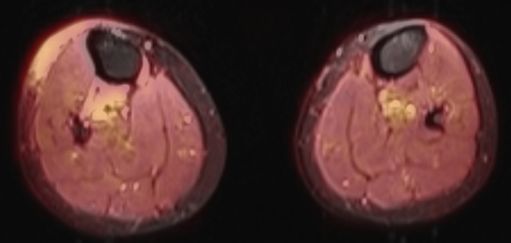

55-jähriger Mann mit einen kutanen Rezidiv eines multiplen Myeloms nach autologer und allogener Stammzelltransplantation mit kompletter Remission. PET-CT: Atypische Plasmazellen durchsetzen Cutis und Subkutis unterhalb der Kniesscheibe, infiltrieren aber nicht die Muskulatur.